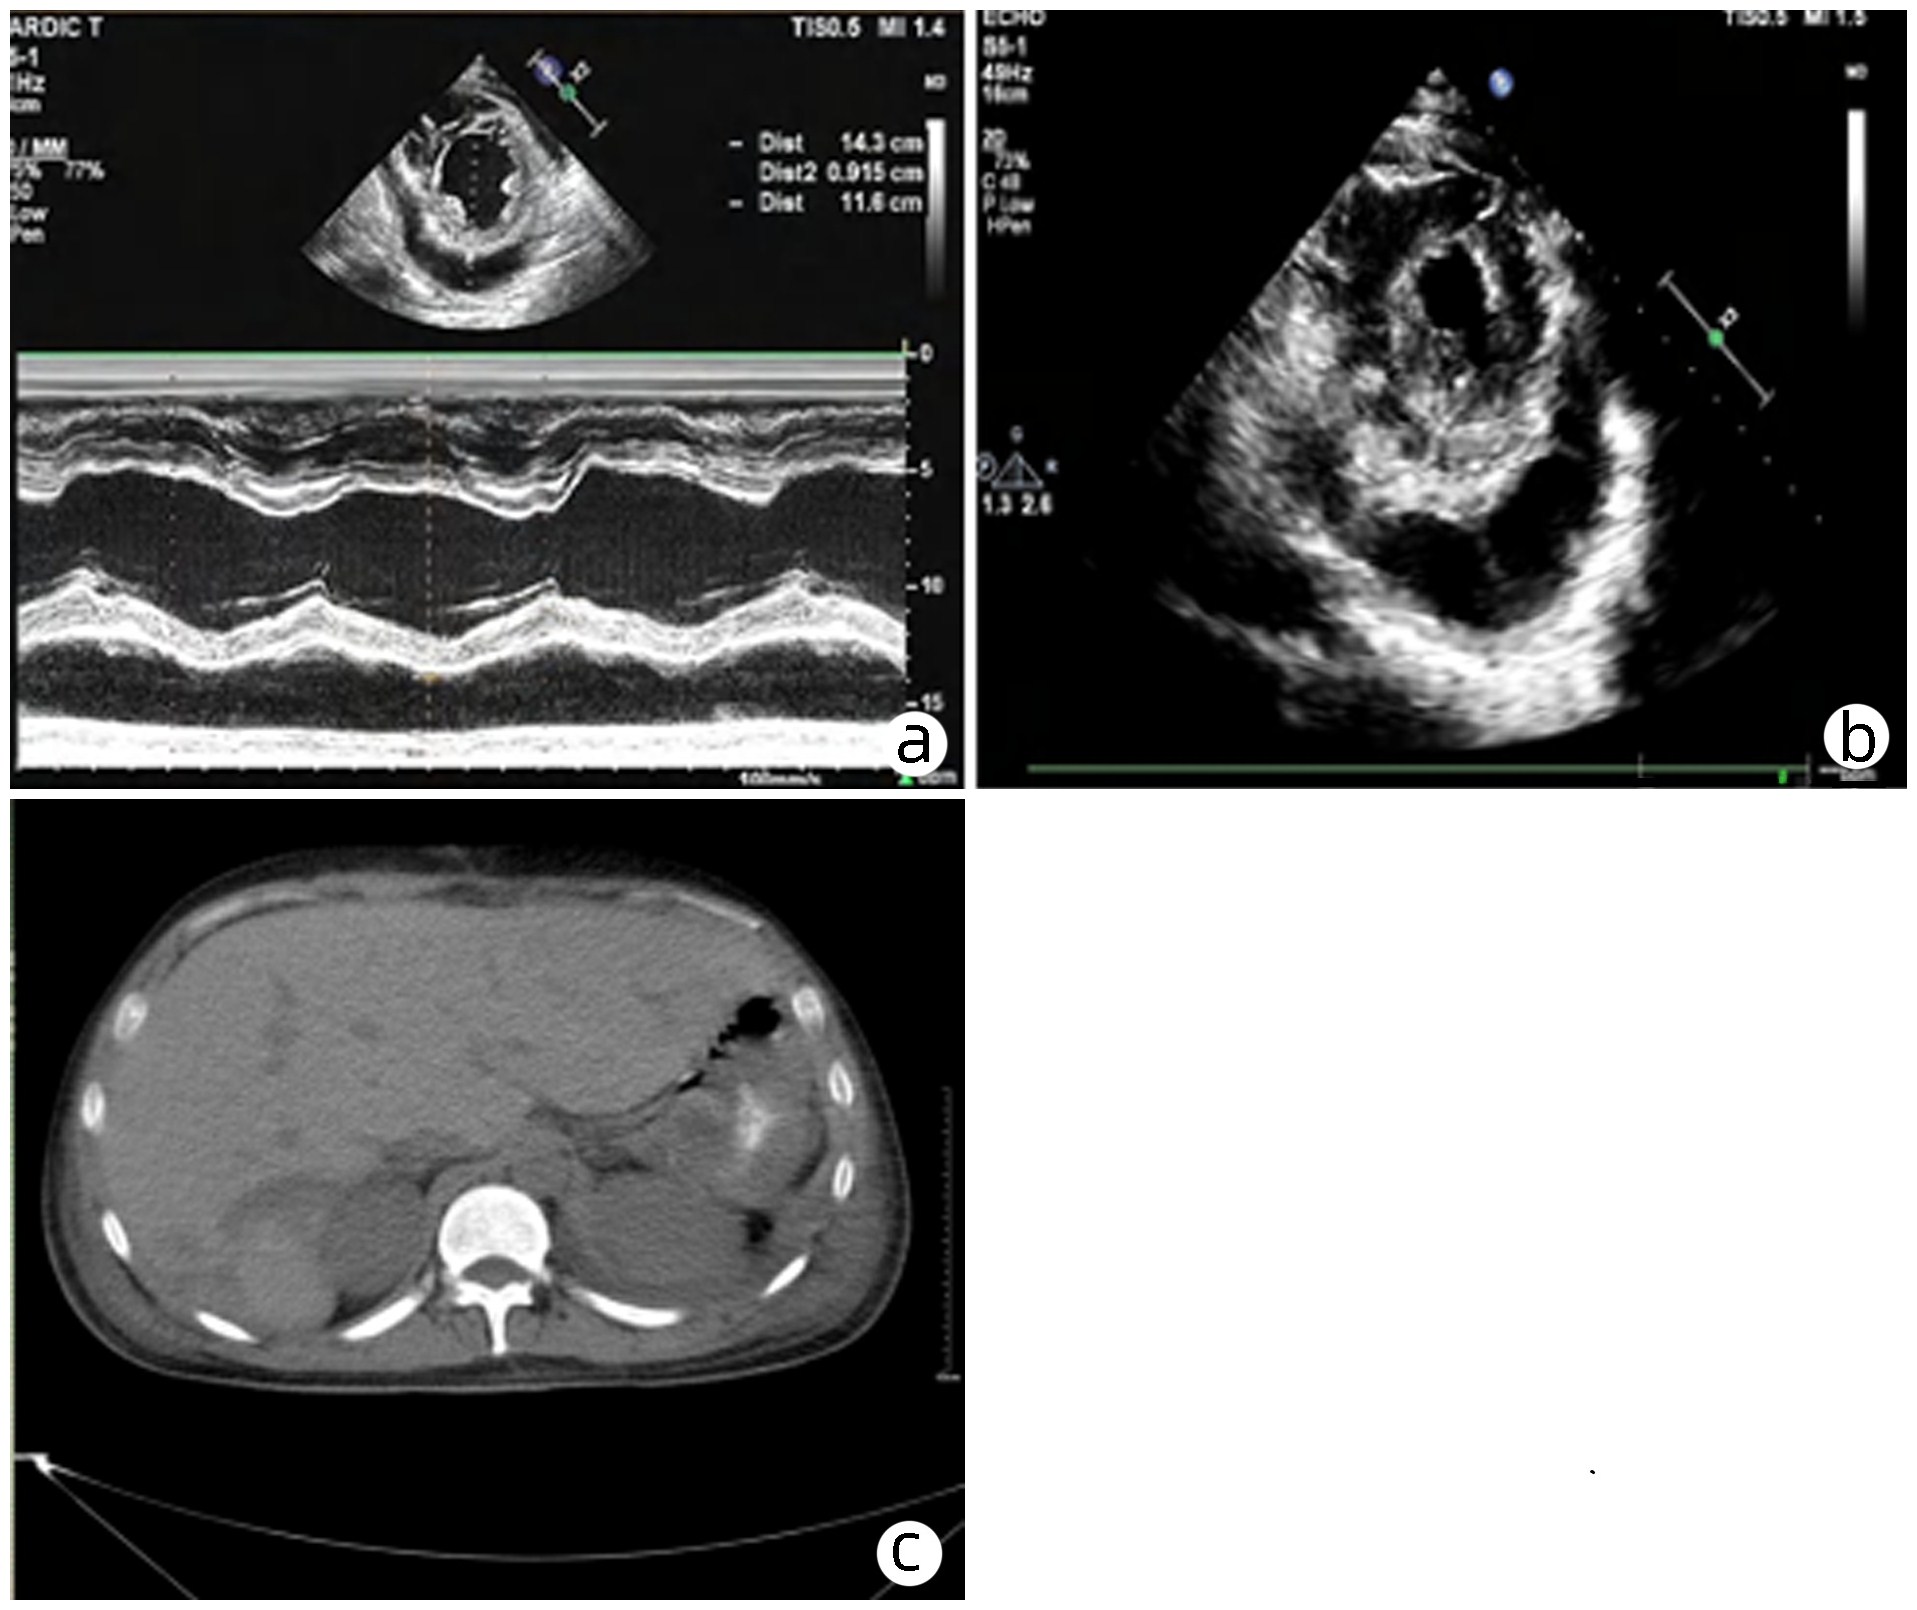

Severe hyperbilirubinemia induced by hereditary spherocytosis: A case report

ABUDUSALAMU·Tuersunmaimaiti, Yunfei ZHANG, Gang YAO, SHADIKE·Apaer, TUERHONGJIANG·Tuxun, Hao WEN

2023, 39(8): 1922-1925. DOI: 10.3969/j.issn.1001-5256.2023.08.023

Abstract(1487) HTML (313) PDF (2217KB)(120)

Abstract:

Hereditary spherocytosis is a type of hereditary hemolytic disease with human erythrocyte membrane defects and has the main symptoms of anemia, jaundice, and splenomegaly. Since its clinical symptoms are not typical, misdiagnosis or missed diagnosis is often observed. At present, there are rare cases with extremely high levels of total bilirubin and direct bilirubin in clinical practice, with few reports in China and globally. In this study, the patient had a total bilirubin level of 1 686.01 μmol/L and a direct bilirubin level of 1 166.6 μmol/L on admission. The patient was successfully discharged after surgical treatment and had good general conditions and high quality of life during follow-up. This article summarizes the experience in the diagnosis and surgical treatment of hereditary spherocytosis.